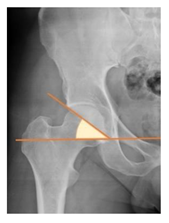

Preoperative and postoperative radiographic data are reported in Table 4. Preoperatively, 18 THR (24.3%) were implanted in skeletally immature children with closed triradiate cartilage (1 ≤ Risser ≤ 3). Radiographic acetabular insufficiency (LCEA < 25° and AI > 13°) was detected in 14 hips (18.9%), while protrusion was present in 3 hips (4.1%) An excessive valgus of the femoral neck was observed in 19 hips (25.7%), while an important varus deformity was present in 7 hips (9.5%).